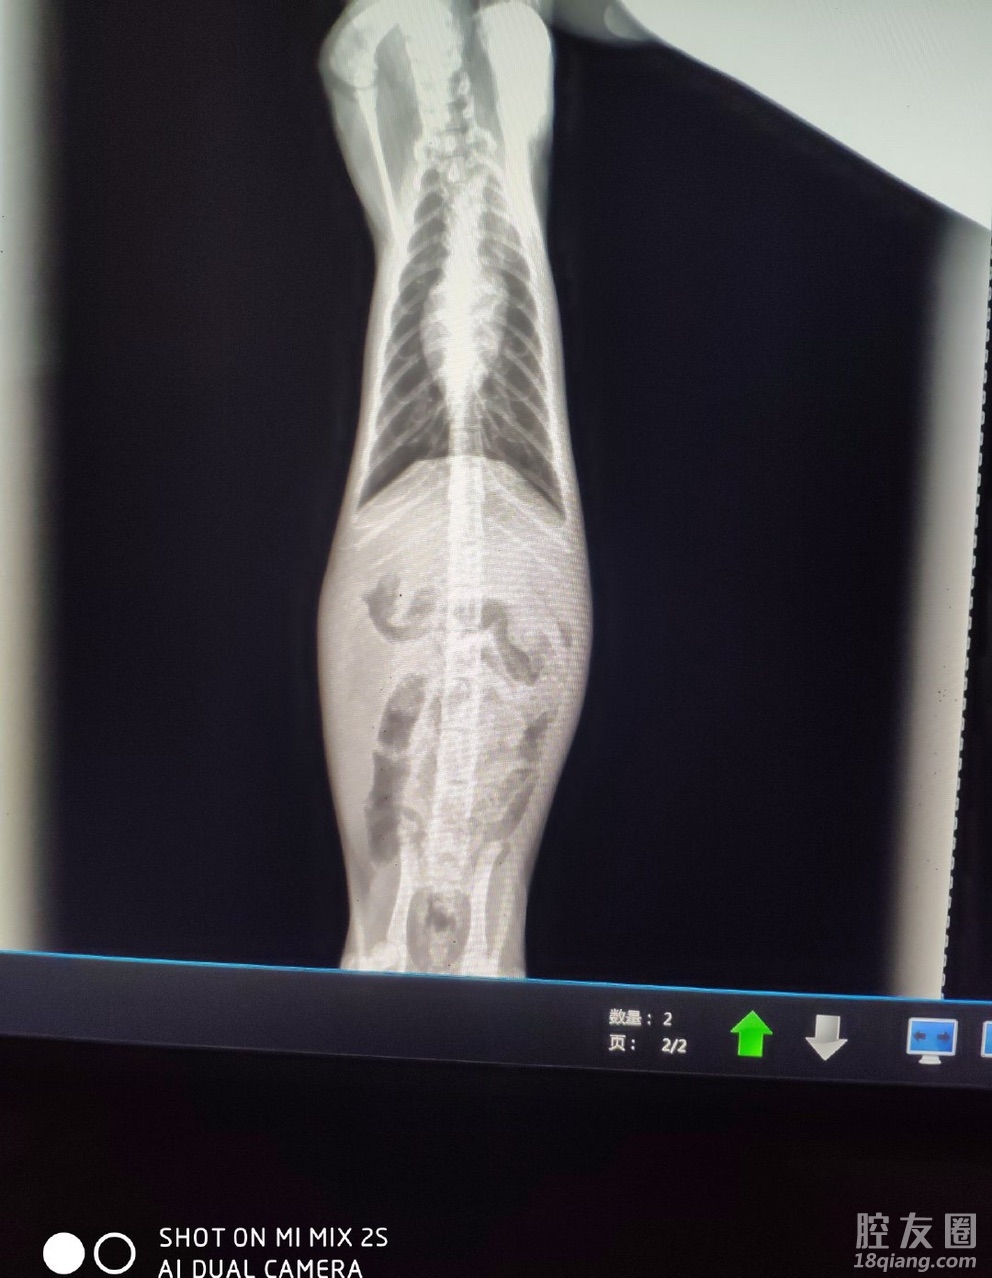

猫传腹到底是需要怎么治

昨天停针今天就发烧

441打了两个多月还是不见好

白蛋白有轻微升高 但未到正常值

贫血及肝肾功能有好转

有经验的宝宝能聊聊吗真的心急